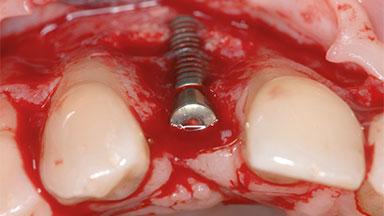

A 35-year old female patient was referred to the Department of Oral Surgery and Stomatology at the University of Bern, Switzerland, for examination of an implant site that had exhibited clinical signs of slightly delayed wound healing. In addition, the referring clinician found no evidence for a facial bone wall when she raised a flap to gain access to the implant for abutment connection. Four months earlier, she had inserted a bone-level implant in a single-tooth gap, where the lateral incisor had been extracted due to a chronic periapical lesion on the mesial aspect of the root. Implant placement was combined with simultaneous bone augmentation using deproteinized bovine bone mineral (DBBM, Bio-Oss®; Geistlich, Wolhusen, Switzerland) and a collagen membrane (Bio- Gide®; Geistlich), followed by primary wound closure. The patient also provided the postsurgical radiograph that displayed the implant with a 3.5-mm healing cap.

Bone Augmentation Horizontal|Simultaneous

Augmentation Materials Autogenous chips|Xenogenous|Membrane

Bone Volume Deficient horizontally, allowing simultaneous augumentation